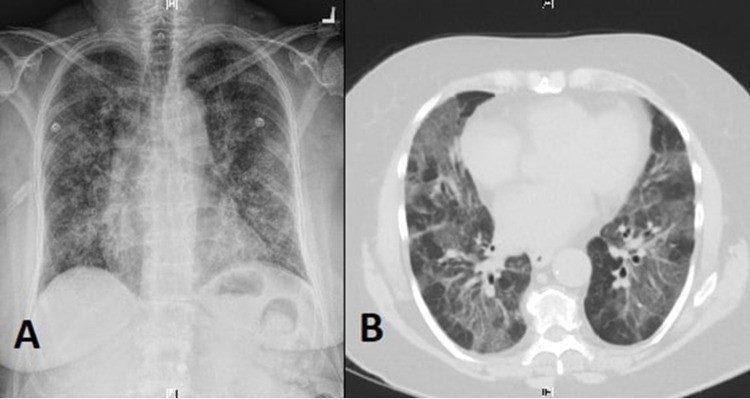

A 66-year-old female with a past medical history significant for chronic obstructive pulmonary disease (COPD) presented to our hospital with acute-onset shortness of breath and dry cough. She reported trying dabbing BHO for the first time 24 hours before the onset of her symptoms. At presentation, she endorsed the presence of dyspnea and dry cough but denied chest pain, palpitations, hemoptysis, lower-extremities swelling, dizziness, or syncopal episodes. She also denied fever, chills, nausea, vomiting, diarrhea, or abdominal pain. She was tachypneic, tachycardiac, and hypoxic with an O2 saturation of 90% on 3 L nasal cannula but afebrile. Physical examination was positive for diffuse pulmonary crackles and scattered wheezes over both lungs’ fields but otherwise unremarkable. Labs showed leukocytosis of 14,300/uL. A chest X-ray showed a diffuse micronodular pattern with patchy infiltrates (Figure 1A). A computed tomography (CT) scan of the chest was done and showed extensive patchy ground-glass opacity throughout both lungs’ fields, suggestive of inflammatory pneumonitis (Figure 1B). Based on the patient’s clinical presentation and the temporal relationship between dabbing and the development of her symptoms, she was diagnosed with hypersensitivity pneumonitis and started on daily 60 mg prednisone for treatment. After three days, her dyspnea and cough improved significantly, and her oxygen requirement went back to normal. A follow-up chest X-ray showed a complete resolution of the infiltrative process. She was discharged home on daily 60 mg prednisone for a total of two weeks, followed by slow tapering with a recommendation to avoid dabbing or any other inhalational cannabinoid usage.

The temporal relationship between BHO exposure and the development of hypersensitivity pneumonitis in our patient is suggestive of a causal relationship. However, the exact underlying pathophysiological mechanism is unclear, but it could be related to direct inhalation injury and maladaptive host immune response induced by butane or other impurities [ref. 15]. Imaging findings in cannabis-induced hypersensitivity pneumonitis among synthetic marijuana users include diffuse centrilobular nodules with a tree-in-bud pattern on chest CT scan and a diffuse micronodular pattern with patchy foci on chest X-ray [ref. 16]. The treatment approach is similar to other cases of hypersensitivity pneumonitis. It includes avoidance of dabbing or any other inhalational cannabinoid usage and corticosteroid therapy, usually with daily 60 mg prednisone for one to two weeks, followed by slow tapering [ref. 17].